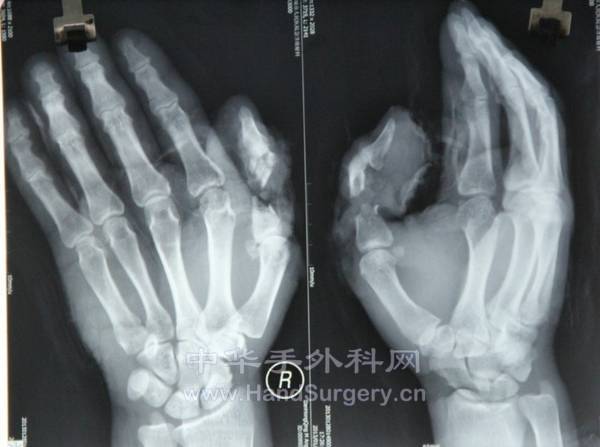

昨天晚上急诊,拇指严重挤压伤,游离腹股沟皮瓣修复术,患者很胖,皮瓣减肥都花了一个多小时,术后仍然不是很满意

术前:

拇指拼起来以后,软组织缺损

设计腹股沟皮瓣修复

腹部脂肪很厚

初步减肥以后

皮瓣断蒂以后

术后血运良好

X线